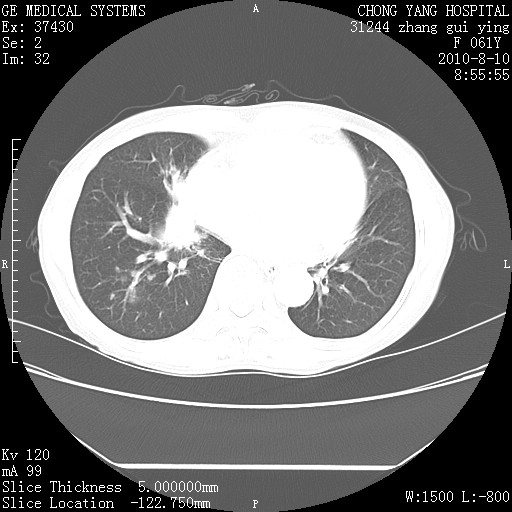

标题: CT28314:F61Y胸部增强,发热咳嗽一周入院,后面的为一周前平 [打印本页]

标题: CT28314:F61Y胸部增强,发热咳嗽一周入院,后面的为一周前平

右肺下叶中心性肺癌可能性大

1、支持考虑右侧中央型肺癌伴右肺中叶节段性不张及下叶支气管黏液痰栓    2、左肺上叶舌段感染。

支持右下肺中央型肺癌并左上肺感染.

我也觉得右肺中叶支气管受累

支持3楼意见,还要考虑:纵隔及肺门淋巴结转移、右侧少量胸腔积液。

确切的说:1:右肺下叶中心型肺癌侵及中叶支气管并中叶不张,纵膈淋巴结转移。2:左肺舌叶炎症。3:右侧胸腔少量积液

块影平扫32hu,动静脉期62-70hu.

1:右肺下叶中心型肺癌侵及中叶支气管并中叶不张,纵膈淋巴结转移。2:左肺舌叶炎症。3:右侧胸腔少量积液。支持!

右肺下叶内基底段近膈不规则肿块,考虑右肺下叶周围型肺癌可能性大。

考虑右下肺肺癌,纵隔淋巴结转移i。

右肺下叶中心型肺癌侵及中叶支气管并中叶不张,纵膈淋巴结转移。2:左肺舌叶炎症。3:右侧胸腔少量积液